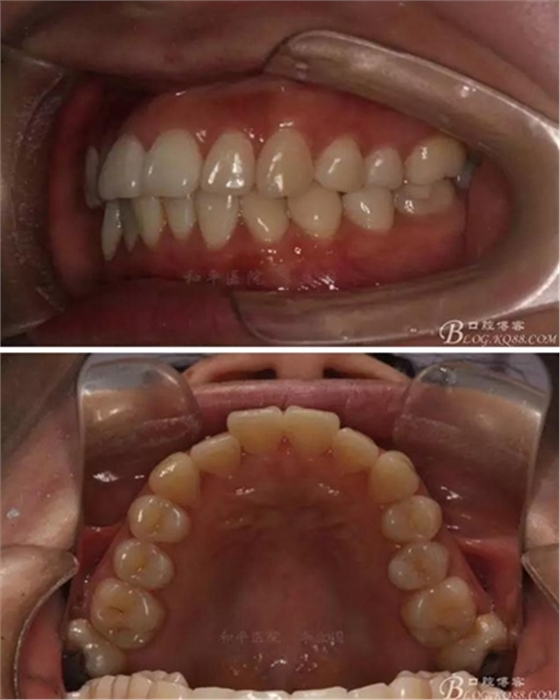

患者,女,主訴:牙齒不齊。

如圖,該病例為簡單排齊病例,但77鎖合是矯治中的關(guān)鍵所在,你會怎么處理?

該病例主要為17、27頰側(cè)位同時伴有伸長,當(dāng)然種植支抗可以解決,但還有簡單實(shí)用的辦法嗎?如圖,在橫腭桿遠(yuǎn)中延伸出牽引鉤,位置盡量遠(yuǎn)離合平面,7粘舌側(cè)扣,牽引力的方向?yàn)閴旱图吧嘞?,下圖為兩個月的效果,17已到位,27還未到位。